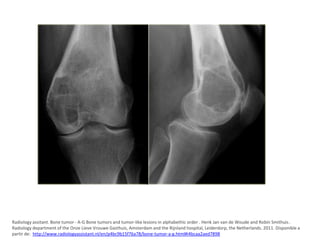

Tumor de células gigantes

• Tumor agresivo, caracterizado por tejido muy

vascularizado, constituido por células ovoides

o fusiformes, y por la presencia de numerosas

células gigantes de tipo osteoclastico

distribuidas de manera uniforme por todo el

tejido tumoral. OMS

• CARACTERISTICAS CLINICAS

– Dolor ,tumefacción y limitación de la movilidad.

– Las fracturas patológicas son hallazgos frecuentes

– Predomina en mujeres entre los 20-40 años de edad.

• DIAGNOSTICO POR IMÁGENES

– Lesiones excéntricas radiolucidas sin borde escleroso, de

limites mal definidos.

– Se ubican en epífisis hasta la región subcondral del

cartílago articular y que se extiende hacia la metafisis.

• CARACTERISTICAS ANATOMO-PATOLOGICAS

– Células gigantes multinucleadas (20 nucleos) y células

mononucleadas.